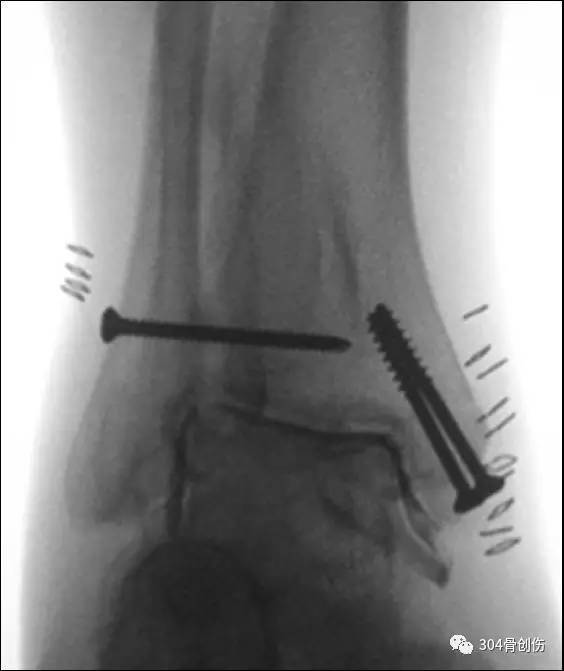

踝部骨折术中如何判断下胫腓分离程度?最常用的就是“拉钩试验(Cotton test)”,透视观察下胫腓之间距离。当下胫腓固定后,胫腓骨远端位置是否妥当?拉钩试验难以评判。最好的方法就是术中CT检查,但目前不是所有的手术室均有术中CT,多是靠术后CT检查后判断,一旦发现下胫腓位置关系不正确,相当一部分需要重新翻修,增加了患者的痛苦,也增加了手术感染风险。简单可靠的评估方式亟需在临床上推广。

术中判定下胫腓稳定

常用的方法-拉钩试验

部分病例术后发现下胫腓关系错误

常常需要再次手术翻修调整

英国Boyd 等人提出在术中判断下胫腓联合损伤或腓骨复位情况的新方法-Chertsey 试验,该文发表在Injury 杂志。

注射针头国际标准

常规手术固定骨折,继而用细穿刺针(22G 腰穿针-相当于6.5号针头,内径0.41mm)在透视下插入踝关节前外侧关节腔,透视踝穴位下注入 2~4 mL 的造影剂(可以1:1盐水稀释)。若造影剂流向下胫腓联合区域,出现「泛溢」现象,说明造影剂渗至损伤的下胫腓联合。若无下胫腓联合损伤,造影剂则局限于踝关节区域,此即 Chertsey 试验阴性。